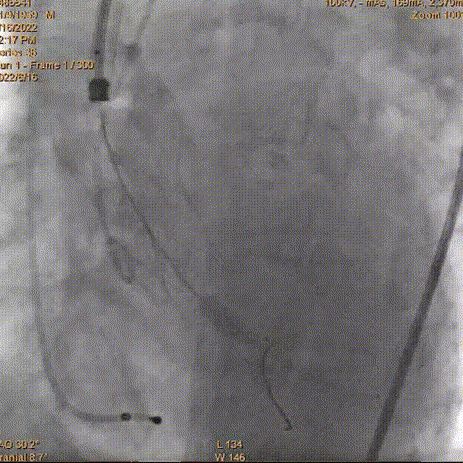

术中影像:

右冠术前造影

右冠术后造影